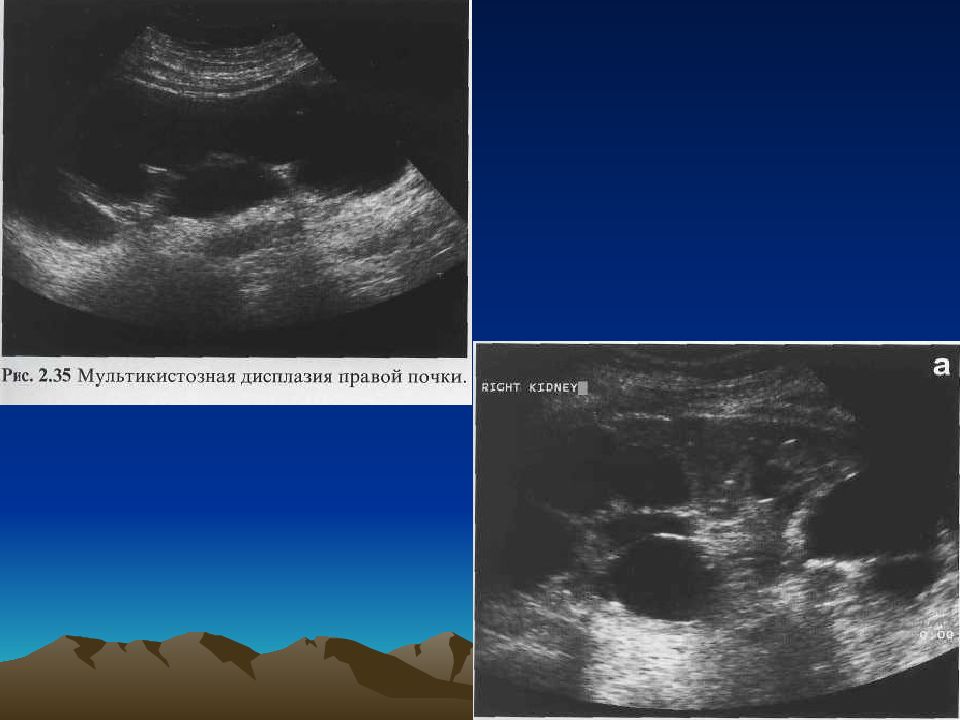

Мультикистозная почек плода